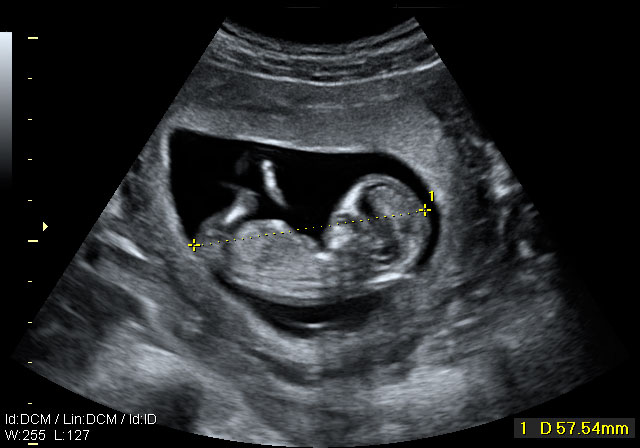

Ecografía 4D de la semana 12: Feto mirando "a la cámara"

Pueden observarse los huesos de la mano

Esta ecografía 4D muestra a un bebé de 12 semanas de gestación que se encuentra situado contra la pared del útero materno. El feto parece mirar varias veces hacia el ecógrafo y se tapa la cara con los brazos. Puede observarse con gran detalle la estructura ósea de la mano.

Ecografía en 4D de un feto de 12 semanas "mirando a la cámara"

A este niño de 12 semanas de gestación parece que le ha "pillado" el ecógrafo desprevenido y se quiere esconder. El bebé está contra la pared uterina: se da cuenta de que el ecografista le está "enfocando" y parece con si se quisiera esconder del público, como las estrellas de cine. Mira varias varias veces "a cámara", en una actitud sorprendente; se tapa la cara con los brazos. La mano se perfila perfectamente, así como muchas de sus estructuras óseas, mientras se esconde cara a la pared uterina.